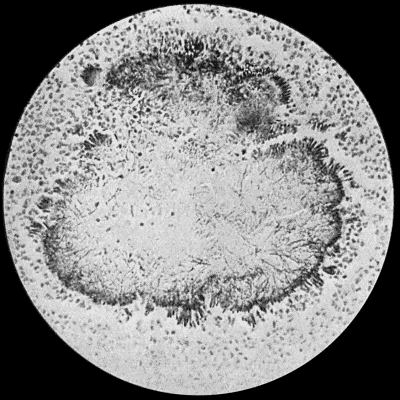

| 30. | Colony of Actinomyces | 126 |

| 31. | Actinomycosis of Maxilla | 128 |